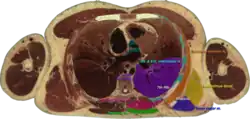

|  Cross section #1428 of the Visible Human Male showing the structures of the triangle of auscultation | |

The superficial floor of the triangle is formed by the lateral portion of the erector spinae muscles. Deep to these muscles are the osseous portions of the 6th and 7th ribs and the internal and external intercostal muscles.

The triangle of auscultation is useful for assessment using a pulmonary auscultation and thoracic procedures.[1] Due to the relative thinning of the musculature of the back in the triangle, the posterior thoracic wall is closer to the skin surface, making respiratory sounds audible more clearly with a stethoscope. On the left side, the cardiac orifice of the stomach lies deep to the triangle. In days before X-rays were discovered, the sound of swallowed liquids were auscultated over this triangle to confirm an oesophageal tumour. To better expose the floor of the triangle up of the posterior thoracic wall in the 6th and 7th intercostal space, a patient is asked to fold their arms across their chest, laterally rotating the scapulae, while bending forward at the trunk, somewhat resembling the fetal position.